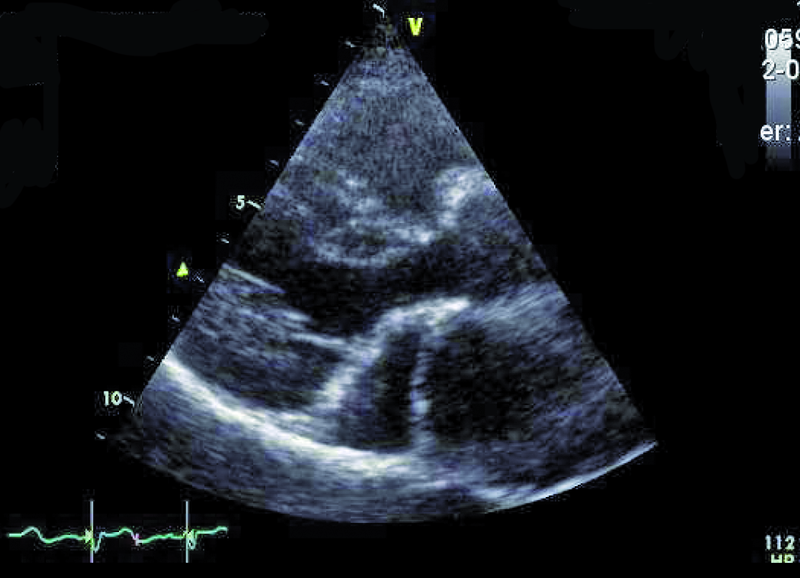

Przedstawiona chora, prawie dorosła kobieta, znajduje się w tej drugiej grupie. Jamy serca są u niej niepowiększone, a mięsień ma prawidłową grubość (ryc. 1). Rozpoznanie membrany w jamie lewego przedsionka z prawidłowym obrazem zastawki mitralnej nie nastręcza trudności. Membranę można dostrzec w wielu projekcjach (ryc. 2-4). Badanie przezprzełykowe pozwala na bardziej precyzyjne określenie średnicy otworu, która zazwyczaj waha się od kilku milimetrów do centymetra. W omawianym przypadku otwór jest duży i na podstawie samej jego wielkości można przypuszczać, że nie powoduje obstrukcji przepływu (membrana w projekcji na rycinie 4 znajduje się powyżej zastawki). Tryb doplera ciągłego (ryc. 5) także nie potwierdza zaburzeń przepływu i trudno się spodziewać, by w takiej sytuacji mogło dojść do podwyższenia ciśnienia w żyłach płucnych, włośniczkach i pniu płucnym. Średnica pnia płucnego (21 mm, ryc. 6) jest dowodem na panujące w nim niskie ciśnienie (nie zarejestrowano w badaniu fali zwrotnej trójdzielnej). Serce trójprzedsionkowe z niskim gradientem śródprzedsionkowym przy braku dodatkowych nieprawidłowości (np. przecieku międzyprzedsionkowego lewo-prawego bądź prawo-lewego – zależnie, z jaką jamą ubytek się komunikuje) nie wymaga leczenia operacyjnego. Pacjentka wymaga dalszej kontroli, ponieważ po wielu latach choroby mogą pojawić się napadowe lub utrwalone nadkomorowe zaburzenia rytmu serca, będące wyrazem zmiany geometrii przedsionka.